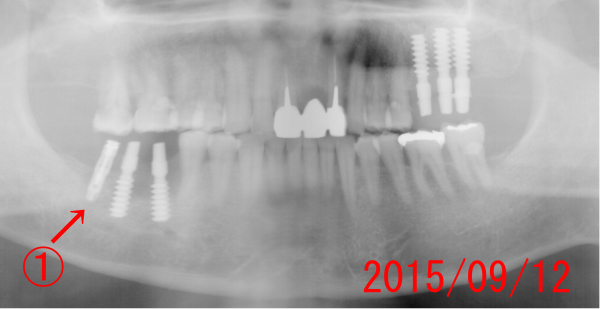

| @:一番奥のインプラントがエミネオです。 それより2本は、ねじ込み式インプラント(4.25mm、Mサイズです。 歯軸を考慮して植立します。従って、すぐにでも最終補綴が印象出来るような角度で植立します。 左上の3本は、先月(08月)に植立。 現在、TEKの状態で、噛んでもらっています。予後良好。 |

| ねじ込み式インプラントに、テック(仮歯)を作り、その日のうちにその場所で食事を出来るよう作ります。 エミネオの部分は、骨と結合するまで数カ月待ちます。歯肉がかぶらないように、エミネオはこの状態で放置します。 |

| 下顎の場合は、患者さんを、少し起こした状態でインプラントを植立するので、誤飲も少なく、患者さんにとっては楽な姿勢で治療します。起こしてした方が、歯軸がよくわかります。 | |